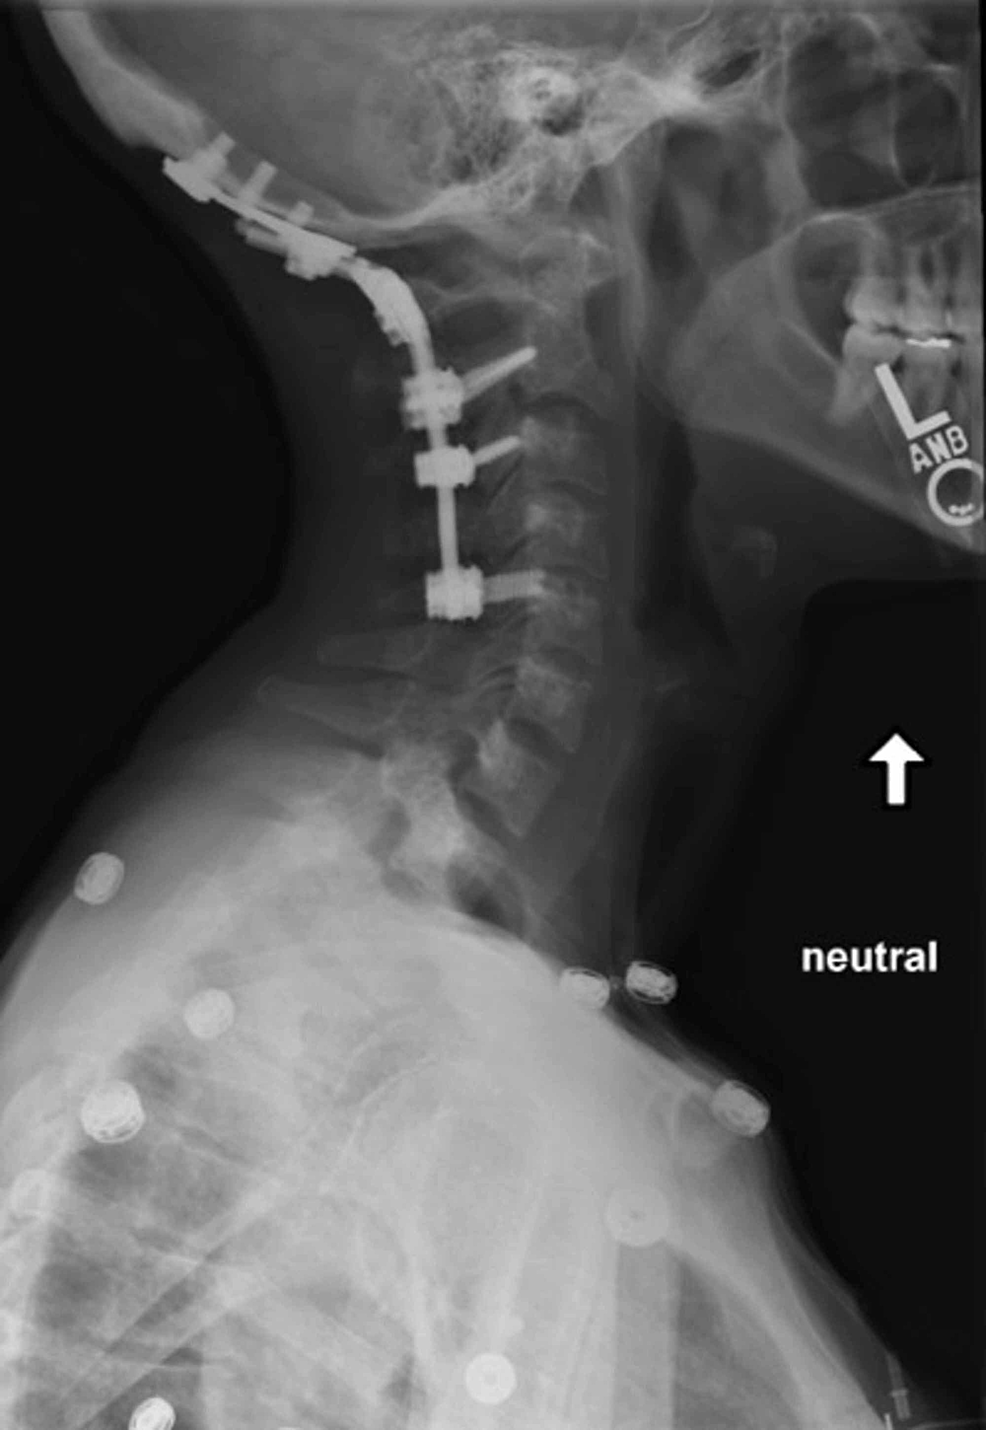

The significance of hardware failure in anterior cervical plate fixation.